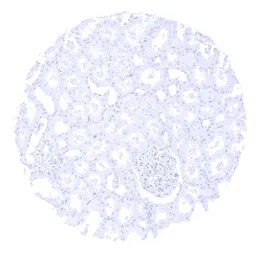

IHC-P analysis of human kidney cortex tissue section using GTX04405 Parathyroid Hormone antibody [MSVA-525R] HistoMAX.

IHC-P analysis of human parathyroid gland tissue section using GTX04405 Parathyroid Hormone antibody [MSVA-525R] HistoMAX.

Parathyroid gland showing intense cytoplasmic Parathyroid Hormone immunostaining of all glandular cells.